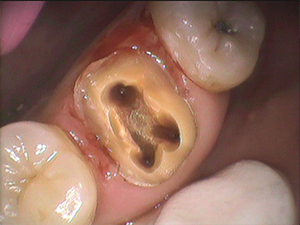

歯の神経を取ったはずなのに痛みが取れない場合は、4本目の歯の神経が見つかっていないのかもしれません

歯の神経を取ったはずなのに痛みが取れない。 治療は終了したと言われたが、どうしても痛みが取れない。 このようなことで吉本歯科医院に駆け込んで下さる患者さんがいらっしゃいます。 歯の神経の入口は 奥歯の場合 通常3つしかな […]

歯の神経治療は歯を失わないための基礎となる重要な治療

えば奥歯の神経(根っこ)の治療、保険治療では歯の神経(根っこ)は3本である、ほとんど3本であるということが、教科書に書かれております。 ですから、歯の根っこの治療(歯の神経治療)は3本までしか算定することができません。 […]